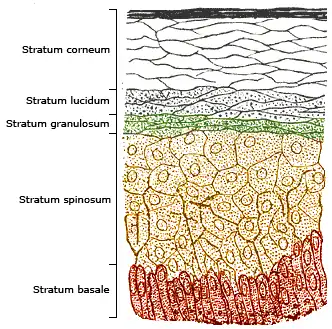

Illustration showing layers of the skin

Protective Epithelia

Prevent exchange between the internal and external environment, examples include:

- skin